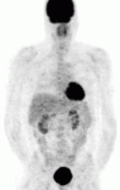

Functional imaging

The imaging modalities discussed below are for tumor characterization, confirmation of metastatic disease, and treatment planning — they are not used to discern tumor location or help the surgical team prepare for excision.[89] For most pheochromocytoma patients, functional imaging will follow a CT or MR. If anatomic imaging only demonstrates an adrenal tumor without evidence of disease anywhere else in the body and the metanephrine levels are overtly elevated, functional imaging can be foregone in favor of prompt surgical excision.[84] Over the last decade, there have been five functional techniques used to evaluate the pheochromocytoma patient (1) 18F-fluorodeoxyglucose positron emission tomography (18F-FDG PET), commonly referred to as the PET scan, (2) iodine-123 meta-iodobenzylguanadine (123I-MIBG), (3) 18F-flurodihydroxyphenylalanine (18F-FDOPA),(4) 68Ga-DOTA coupled somatostatin analogs (68Ga-DOTA),(5) 11C-Hydroxy ephedrine(HED-PET). From this point forward, these imaging modalities will be referred to in their abbreviated names found in parentheses.

Of the four above mentioned modalities, 18F-FDG PET is the most common and readily available functional imaging technique at most hospital systems, but the least-specific to neuroendocrine tumors (Image Left). In 2012, over 200 patients participated in a trial that compared the current gold standard of the time (MIBG/CT/MRI) to the novel FDG PET. Compared to its functional counterpart, FDG outperformed MIBG in detecting soft-tissue and bone metastases with higher specificity in patients with biochemically active tumors.[80]